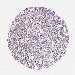

PANCREATIC CANCER - Protein expressioni

A mouse-over function shows sample information and annotation data. Click on an image to view it in a full screen mode. Samples can be filtered based on level of antibody staining by selecting one or several of the following categories: high, medium, low and not detected. The assay and annotation is described here.

Note that samples used for immunohistochemistry by the Human Protein Atlas do not correspond to samples in the TCGA dataset.

Antibody stainingi

Antibody staining in the annotated cell types in the current human tissue is reported as not detected, low, medium, or high, based on conventional immunohistochemistry profiling in selected tissues. This score is based on the combination of the staining intensity and fraction of stained cells.

Each image is clickable and will lead to virtual microscopy that enables deeper exploration of all samples and also displays staining intensity scores, fraction scores and subcellular localization as well as patient and tissue information for each sample.

Antibody HPA043823

Antibody CAB069427

Staining

High

Medium

Low

Not detected

Intensity

Strong

Moderate

Weak

Negative

Quantity

>75%

75%-25%

<25%

None

Location

Nuclear

Cytoplasmic/membranous

Cytoplasmic/membranous,nuclear

Adenocarcinoma, NOS